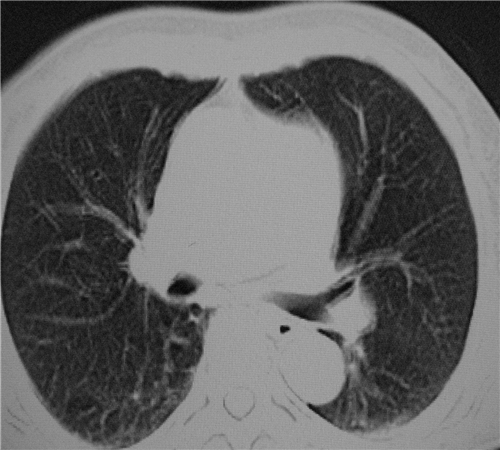

标题: CT26849:女67岁反复胸痛两天余,临床考虑夹层。 [打印本页]

标题: CT26849:女67岁反复胸痛两天余,临床考虑夹层。

右肺感染,未见夹层。

既然考虑夹层,建议强化!另:右下肺感染!

1)右肺感染性病变。2)建议行ct增强扫描或mri检查排除主动脉夹层。

双下肺感染,右侧显著。有无夹层,增强扫描后再诊断。

1. 感染性病变,2.未见夹层,3.食道未见异常。